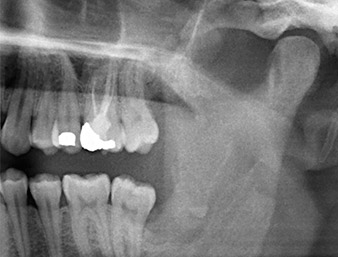

OPG 6 months after osteotomy

Fig. 1: OPG 6 months after osteotomy of tooth 38 (LL8): radix relicta lies close to the inferior alveolar nerve.

The root remnant in the region of tooth 38 (LL8) was already displaying close proximity to the inferior alveolar nerve on the OPG. The root had fractured during the osteotomy but had not been removed by the primary treatment provider due to intraoperative pain. To ensure as little trauma as possible to the tissue, the new osteotomy was to be carried out using a piezo surgical system. The patient had an unremarkable medical history and was a non-smoker.

It could be seen in the 3D image (digital volume tomography) that the root remnant was located disto-caudally in the transition from the horizontal to the ascending portion of the mandible (Fig. 2).